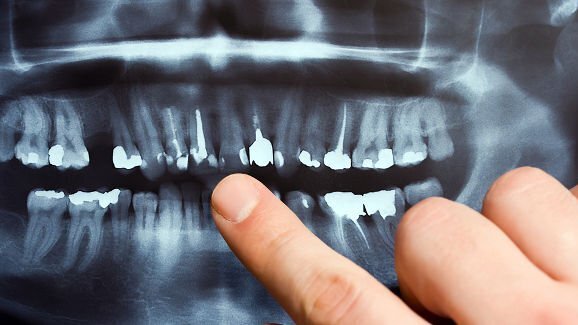

Podobne konsekwencje może też mieć źle wykonane leczenie kanałowe, czy źle wszczepiony implant zęba. „Dzięki nowoczesnym technikom obrazowania, jak tomografia trójwymiarowa, obserwujemy u pacjentów po leczeniu kanałowym, że do ich zatok dostały się np. odłamki korzenia, amalgamatu, materiał z wypełniania kanałów” – wymienia dr Michalik. Zatoka reaguje na te ciała obce typowym procesem zapalnym, który objawia się bólami głowy, temperaturą, wydzieliną ropną. Jeśli przejdzie on w stan przewlekły, może spowodować poważne powikłania, groźne dla zdrowia, a nawet życia, w tym zapalenia kości szczęki, powikłania oczodołowe i wewnątrzczaszkowe. Michał Michalik zaznacza, że możliwy jest również proces odwrotny – przewlekłe zapalenie zatok, zwłaszcza zatoki szczękowej, przyczynia się do problemów stomatologicznych. „Jeżeli wówczas wstawimy implant zębowy, to zaczną się problemy z gojeniem tego miejsca, a implant może nawet wypaść” – wyjaśnia specjalista. Podkreśla, że jeśli stomatolog, który przygotowuje pacjenta do wszczepiania implantu, zobaczy w badaniu pantomograficznym jakieś zmiany w zatoce, to powinien odesłać go do laryngologa z prośbą o opinię na temat możliwości wykonania takiej procedury.

„Zabiegi stomatologii estetycznej, a także procedury implantacyjne i leczenie endodontyczne powinny być obszarami ścisłej współpracy lekarzy dentystów z laryngologami. Dobro pacjenta wymaga, byśmy zatok nie traktowali w oderwaniu od leczenia stomatologicznego” – podkreśla dr Michalik dodając, że obecnie możliwe jest wykonywanie zabiegów laryngologicznych i stomatologicznych jednoczasowo, co znacznie skraca czas leczenia. Zdaniem dr. Michalika, ze względu na starzenie się społeczeństwa, implantoprotetyka cieszy się w Polsce coraz większą popularnością, dlatego współpraca stomatologów z laryngologami na tym polu będzie zyskiwała na znaczeniu. Specjalista zwraca też uwagę, że w ostatnim czasie interdyscyplinarność leczenia pacjentów zaczyna być coraz bardziej doceniana. „Laryngolodzy zaczynają coraz ściślej współpracować np. z kardiologami czy seksuologami, bo okazuje się, że problemy laryngologiczne, np. powodujące bezdech senny, negatywnie wpływają na nasze libido, a nawet mogą powodować objawy typowe dla arytmii serca” – podsumowuje.